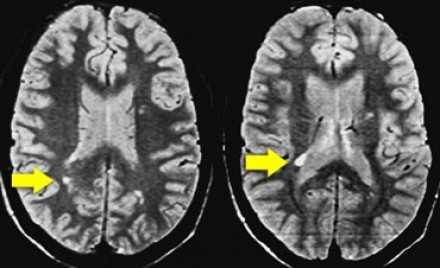

На серии МР-томограмм: множественные гиперинтенсивные участки в белом веществе головного мозга у пациента, страдающего гипертонической болезнью.

На МР-томограммах, представленных выше, визуализируются нарушения МР-сигнала в глубоких отделах больших полушарий. Важно отметить, что они не являются юкставентрикулярными, юкстакортикальными и не локализуются в области мозолистого тела. В отличие от рассеянного склероза, они не затрагивают желудочки мозга или кору. Учитывая, что вероятность развития гипоксически-ишемических поражений априори выше, можно сделать заключение о том, что представленные очаги, вероятнее, имеют сосудистое происхождение.